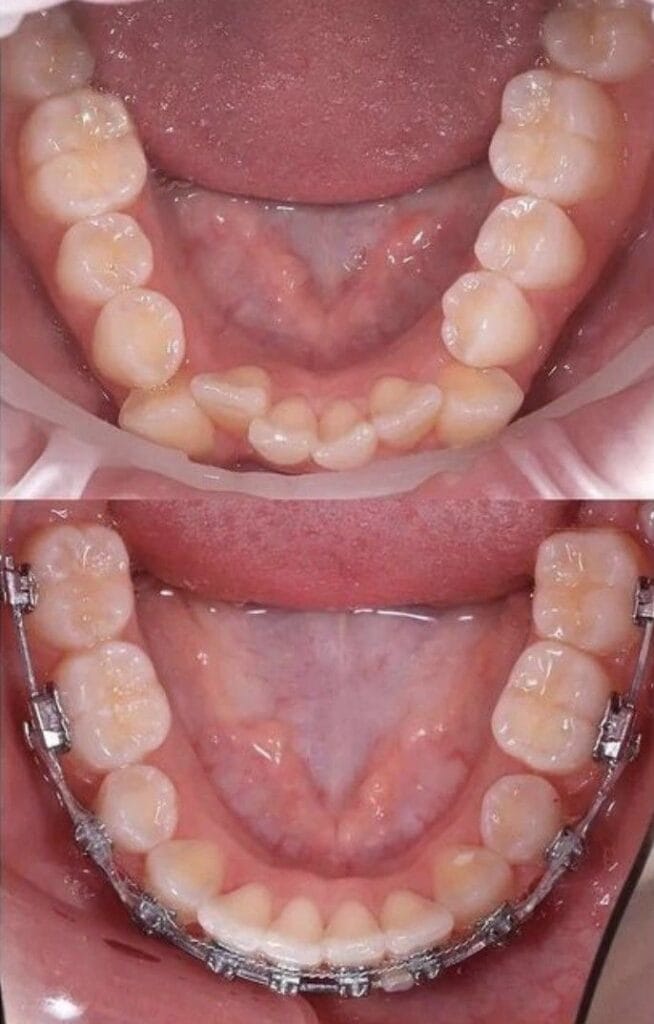

تقويم الأسنان

- تركيب تقويم الأسنان التقليدي أو الشفاف.

- تعديل وضع الأسنان والفكين لتحسين المحاذاة.